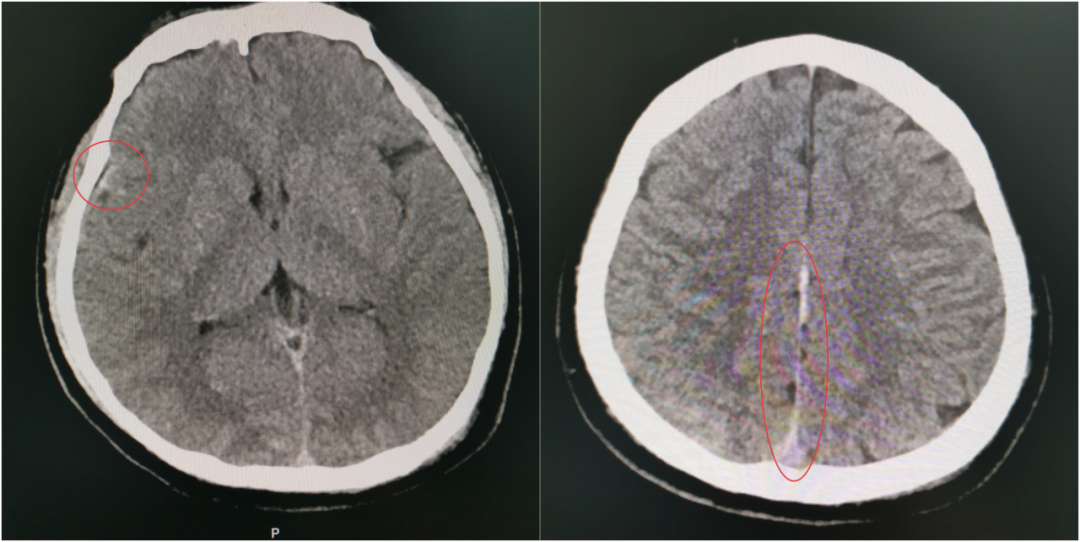

当第二次 CT 提示出现硬膜外血肿、蛛网膜下腔出血范围进一步扩大时,虽然符合预判,但每个人都清楚:出血量和点位的不可控,血肿扩大可能压迫脑组织,任何微小变化都可能改写结局,之前的一系列努力可能功亏一篑。

伤情再次变化,出血范围扩大

这一“激战”持续到次日清晨8点,于如同教授亲自到ICU查房,他仔细审阅了所有的检查和监护数据后,欣慰地确认:“颅内情况稳定了,出血控制得很好,暂时不需要手术。接下来,继续在ICU密切观察,精心护理,帮助他稳定恢复。”